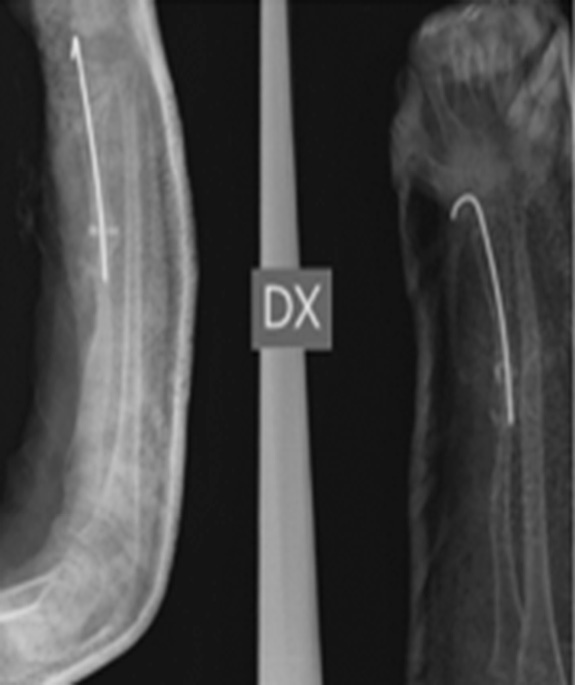

Была выполнена биопсия кости, и по заключению двух разных итальянских центров синдром Горхема – Стоута был исключен, так как выявлены реактивная костная ткань с аномальной васкуляризацией, некротические костно-хрящевые фрагменты и гигантские мононуклеарные клетки. Несмотря на то что пациент поступил в нашу больницу с этими результатами, было решено повторить биопсию, и исключение синдрома Горхема – Стоута было подтверждено. После этого провели дополнительные лабораторные исследования и консультации с большим количеством специалистов, чтобы исключить все причины, которые могли привести к обширному остеолизу. Спустя 11 мес. после последней травмы произведена новая операция на месте перелома с иссечением ткани и имплантированием аутологичного трансплантата малоберцовой кости с факторами роста костного мозга. Трансплантат стабилизирован спицами Киршнера (рис. 4).

Рис. 4. Рентгенограмма до и после иссечения ткани, аутологичная малоберцовая кость с костномозговыми факторами роста, аутотрансплантат стабилизирован интрамедуллярной спицей Киршнера